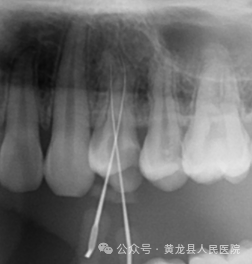

由于牙齿下部隐藏在牙槽骨中,口腔医生要了解牙齿的整体情况就需要拍摄全景片;要了解个别牙根及周围变化,则选择拍摄小牙片或根管CT。医生要判断牙槽骨是否符合种植条件,或者了解埋伏阻生齿的三维位置以及其他颌骨内病变组织的形态大小时,则需要进一步拍摄 CBCT 。

所以,拍牙片是一种帮助牙科医生进行诊断、治疗、疗效评估的重要手段,治疗前用于发现病变程度、范围;治疗中用于引导治疗、确定治疗范围和深度;治疗后用于观察疗效。